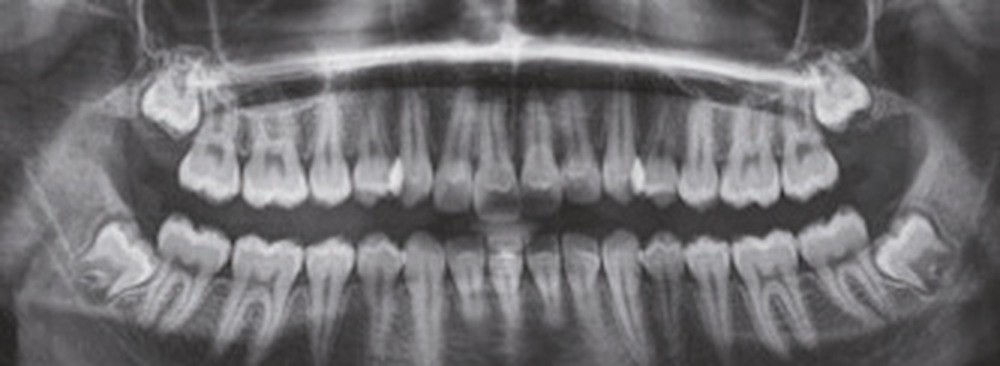

Examen clinique (fig. 1 à 7)

À la vue de l’examen radiographique, elle est au stade CS6 d’après la méthode de maturation vertébrale de Baccetti [1]. Elle présente une classe II squelettique de Ballard par rétrognathie mandibulaire avec un ANB de 9° et un AoBo de 9 mm sur un schéma facial normo-divergent. L’incisive mandibulaire est vestibulo-versée (IMPA = 114°). Le maxillaire est bien positionné. Elle présente de plus une dysharmonie dento-dentaire (DDD) antérieure par excès mandibulaire.